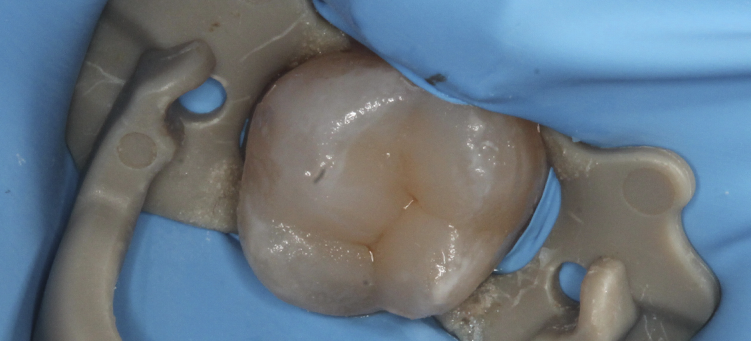

Лечение кариеса зубов